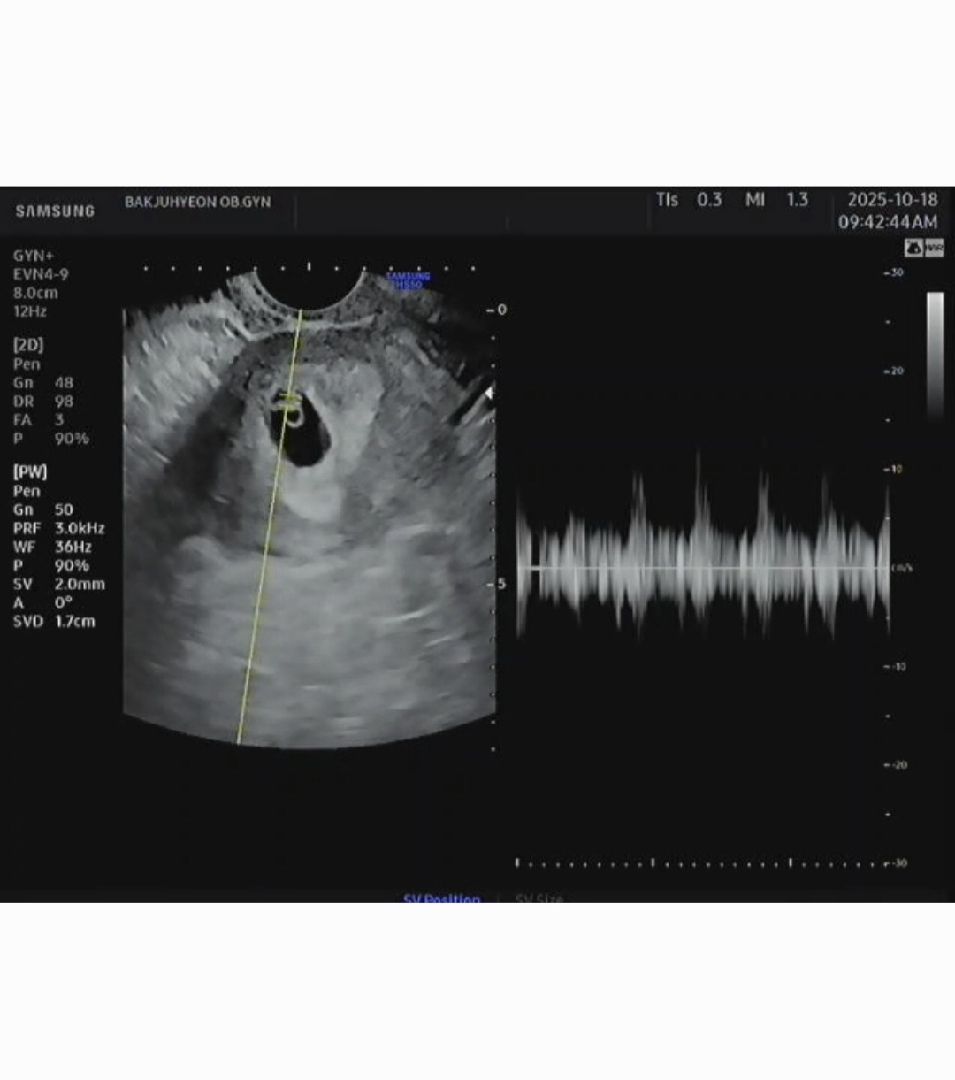

6주 3일차 깨망이 심소 듣고 왔어요!! 깨망이 키도 쟀는데 6.6mm?..6.4..? 옴총 조그마한데 심장소리가 들리니 기분이 이상하더라구요!ㅎㅎ 129bpm 으로 건강이상무래요!!ㅎ저는 결국 입덧약 처방 받았는데 제발 효과있기를..바래봅니댜..🥲🥲